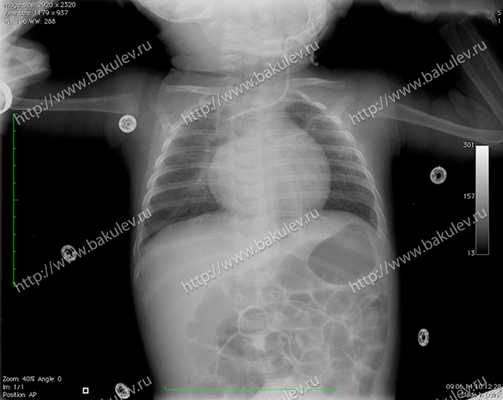

Рентгенография органов грудной клетки: лёгочные поля вздуты. Очаговые и инфильтративные тени не определяются. Сердце расположено срединно, в поперечнике расширено в обе стороны. Кардиоторакальный индекс (КТИ) — 60%.

Рис 3 — Рентгенография органов грудной клетки